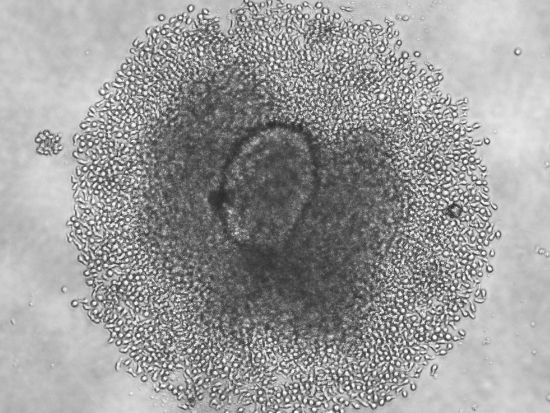

Babon et al., Nature Medicine, 2016

Outgrowth of T cells from an islet remnant from an isolated and handpicked islet, after culture with T cell stimulation and growth factors, from donor nPOD69, a six year old female with three years of type 1 diabetes, is shown.